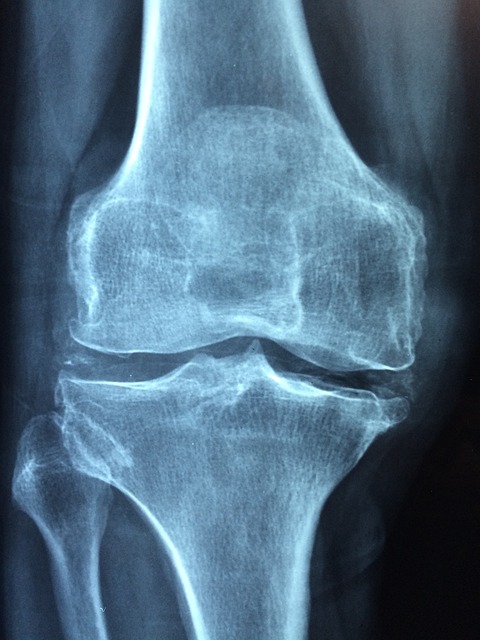

무릎에 물이 차는 이유는 다양합니다. 주로 반복적인 달리기로 인한 연골 손상, 인대 염증, 관절염 등이 원인입니다. 무릎에 부하가 쌓이면서 관절액이 과도하게 분비되는 것입니다.

이런 상태를 무시하고 달리면 작은 통증이 큰 부상으로 이어질 수 있어 주의해야 합니다.